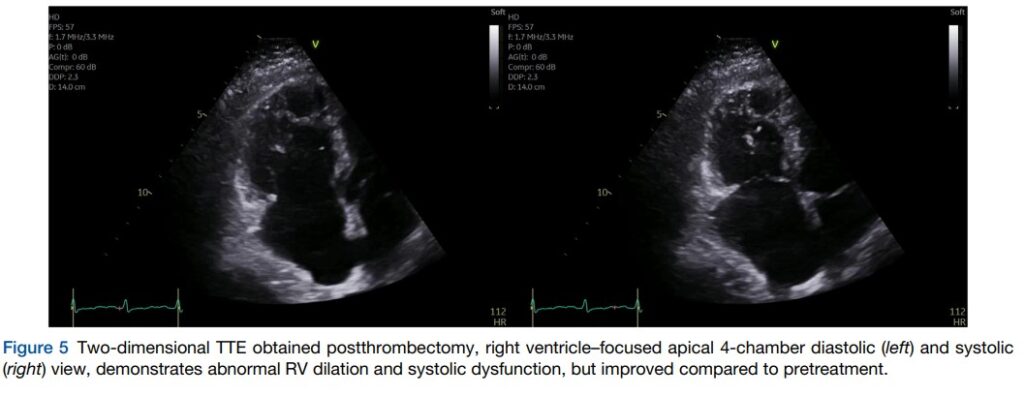

Novo ecocardiograma, realizado após dois dias da trombectomia, mostrou melhora da função sistólica segmentar e global do VD, com aumento do strain de parede livre para 15.8%.